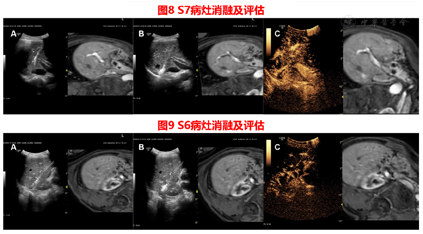

胆囊切除术前CT检查发现肝内病灶,胆囊切除术中病理结果证实S4段病灶为神经内分泌瘤,胆囊切除术后MRI确定剩余病灶,US-MRI容积导航影像融合联合超声造影进行病灶定位、引导、术后评估。

术后消融病灶缩小,增强CT检查未见强化。

患者在2020年9月3日送手术室在复合麻醉下行US-MRI容积导航影像融合引导下经皮肝肿瘤微波消融治疗,见图8,图9。

术后患者病情稳定,恢复良好,已出院。之后规律复查。2021年5月16日MRI结果见图10,图11。

本例患者在常规超声未发现异常病灶,于是在融合成像辅助定位下,对磁共振对应区域进行超声造影,确定了病灶位置,进行消融及术后即时评估。术后患者规律复查,消融效果良好,病灶未见活性。